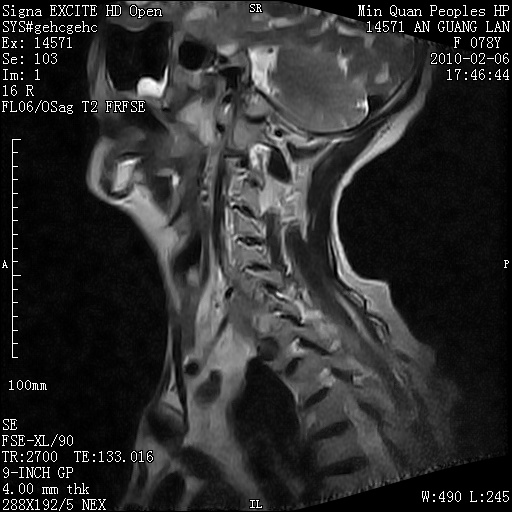

标题: MRI2763:C6、C7椎体病变性质?

f,78y,颈部与双上肢阵发性剧痛40余天。ct可见c6、c7椎体虫蚀样破坏,其间椎间隙变窄(没有图片资料可供上传)。

考虑椎体结核并椎旁脓肿。

支持 c6、7椎体结核并椎旁冷脓肿形成。

考虑:c6/7椎体结核并椎旁脓肿形成,建议增强扫描。